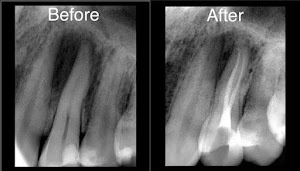

Welcome to our gallery

See how our company transforms ideas into reality. This gallery is a visual testament to our work and achievements.